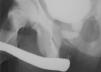

Case 2. Male aged 9 years with pelvic and urethral trauma (bicycle fall). The initial management consisted of a permanent suprapubic catheter. End-to-end urethroplasty was performed at 2 months post-surgery, with the stricture recurring. A second urethroplasty (buccal mucosa graft) was performed one year later and was unsuccessful (the stricture recurred), with recurrent orchitis. Two and a half years after the accident, it was decided to perform an endoscopic urethrotomy (Fig. 1), and the stricture recurred again. Two end-to-end urethroplasties followed (bulbomembranous urethra) at 4 and 5 years post-surgery. Six years after the surgery, and one year after the latest urethroplasty, the patient was asymptomatic and the urethral stricture had not recurred.